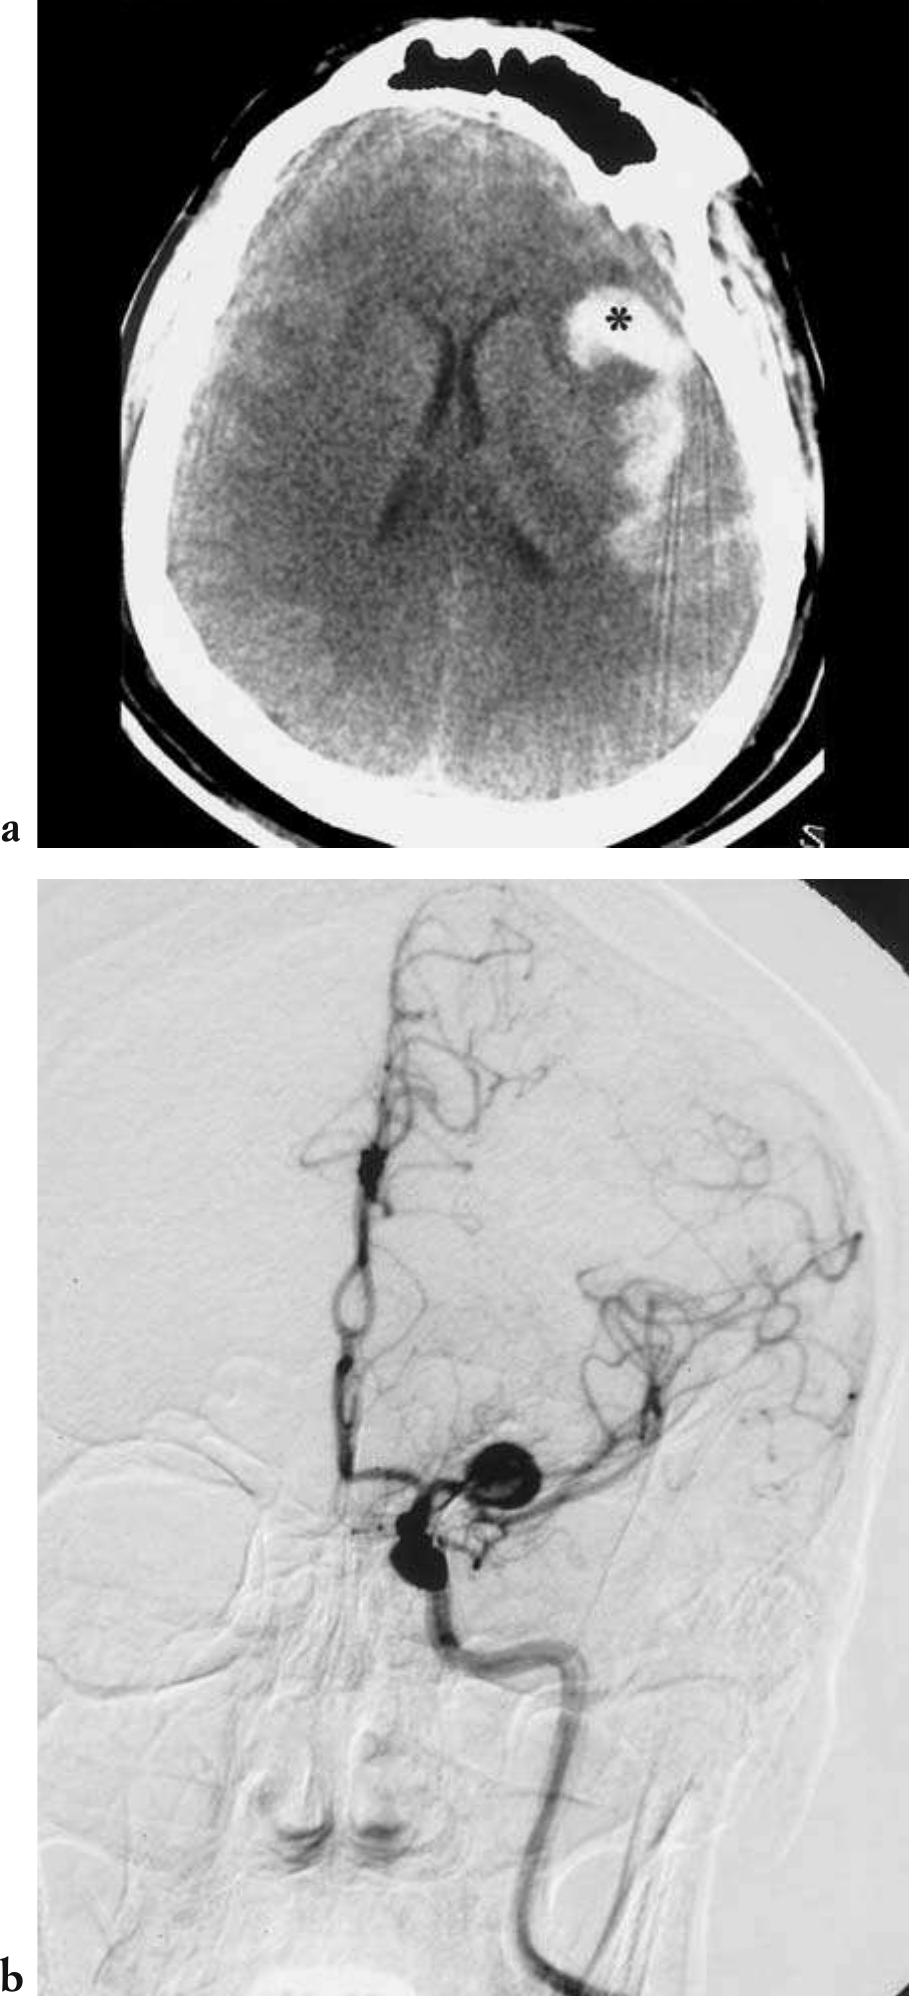

![— CT is the preferred method of imaging in co- ma patients due to its very rapid examination acquisition speeds, with single or multiple slice scanning times faster than one second in latest generation appliances; in addition to its gener- al diagnostic capabilities, it is also very sensitive in recognizing acute and hyperacute phase in- tracranial haemorrhages, in localizing the cra- nial compartment of the bleed (e.g., subdur- al/epidural, subarachnoid, intraparenchymal); finally it is almost universally available in the Fig. 4.17 - Acute hydrocephalus in a case of spontaneous subarachnoid haemorrhage. Unenhanced cranial CT shows an intra- ventricular blood clot at the level of the foramina of Monro and the symmetrical subarachnoid haemorrhage. Also note the di- latation of the lateral ventricles, including the temporal horns, as a consequence of the obstructive hydrocephalus. [a-c) unen- hanced axial CT]](https://figures.academia-assets.com/35610716/figure_279.jpg)